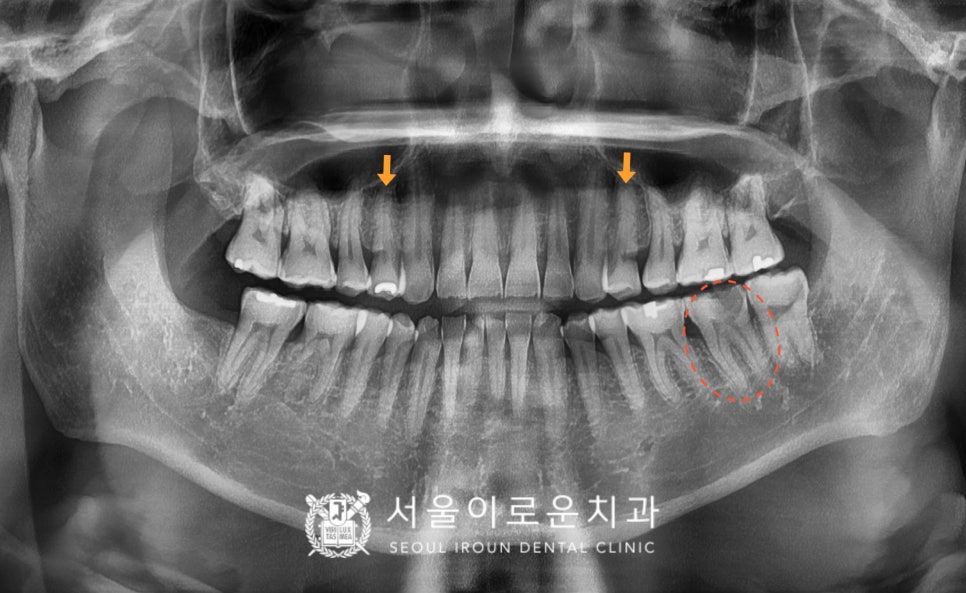

정밀한 검사를 위해

파노라마 사진을 촬영하여

확인해 보았더니

빨간색 동그라미 표시의

아래턱 왼쪽 두 번째 큰 어금니(#37)

머리 부분이 까맣게 비춰보이는것을

확인할 수 있었는데요.

기존 수복물이 탈락되어 있었으며,

하방으로는 2차 우식이

깊게 진행되어 있었습니다.

x-ray 상 치아 안쪽 신경조직까지

충치가 진행되어 있는 상태로

신경치료 후 크라운 수복이 필요하였는데요.